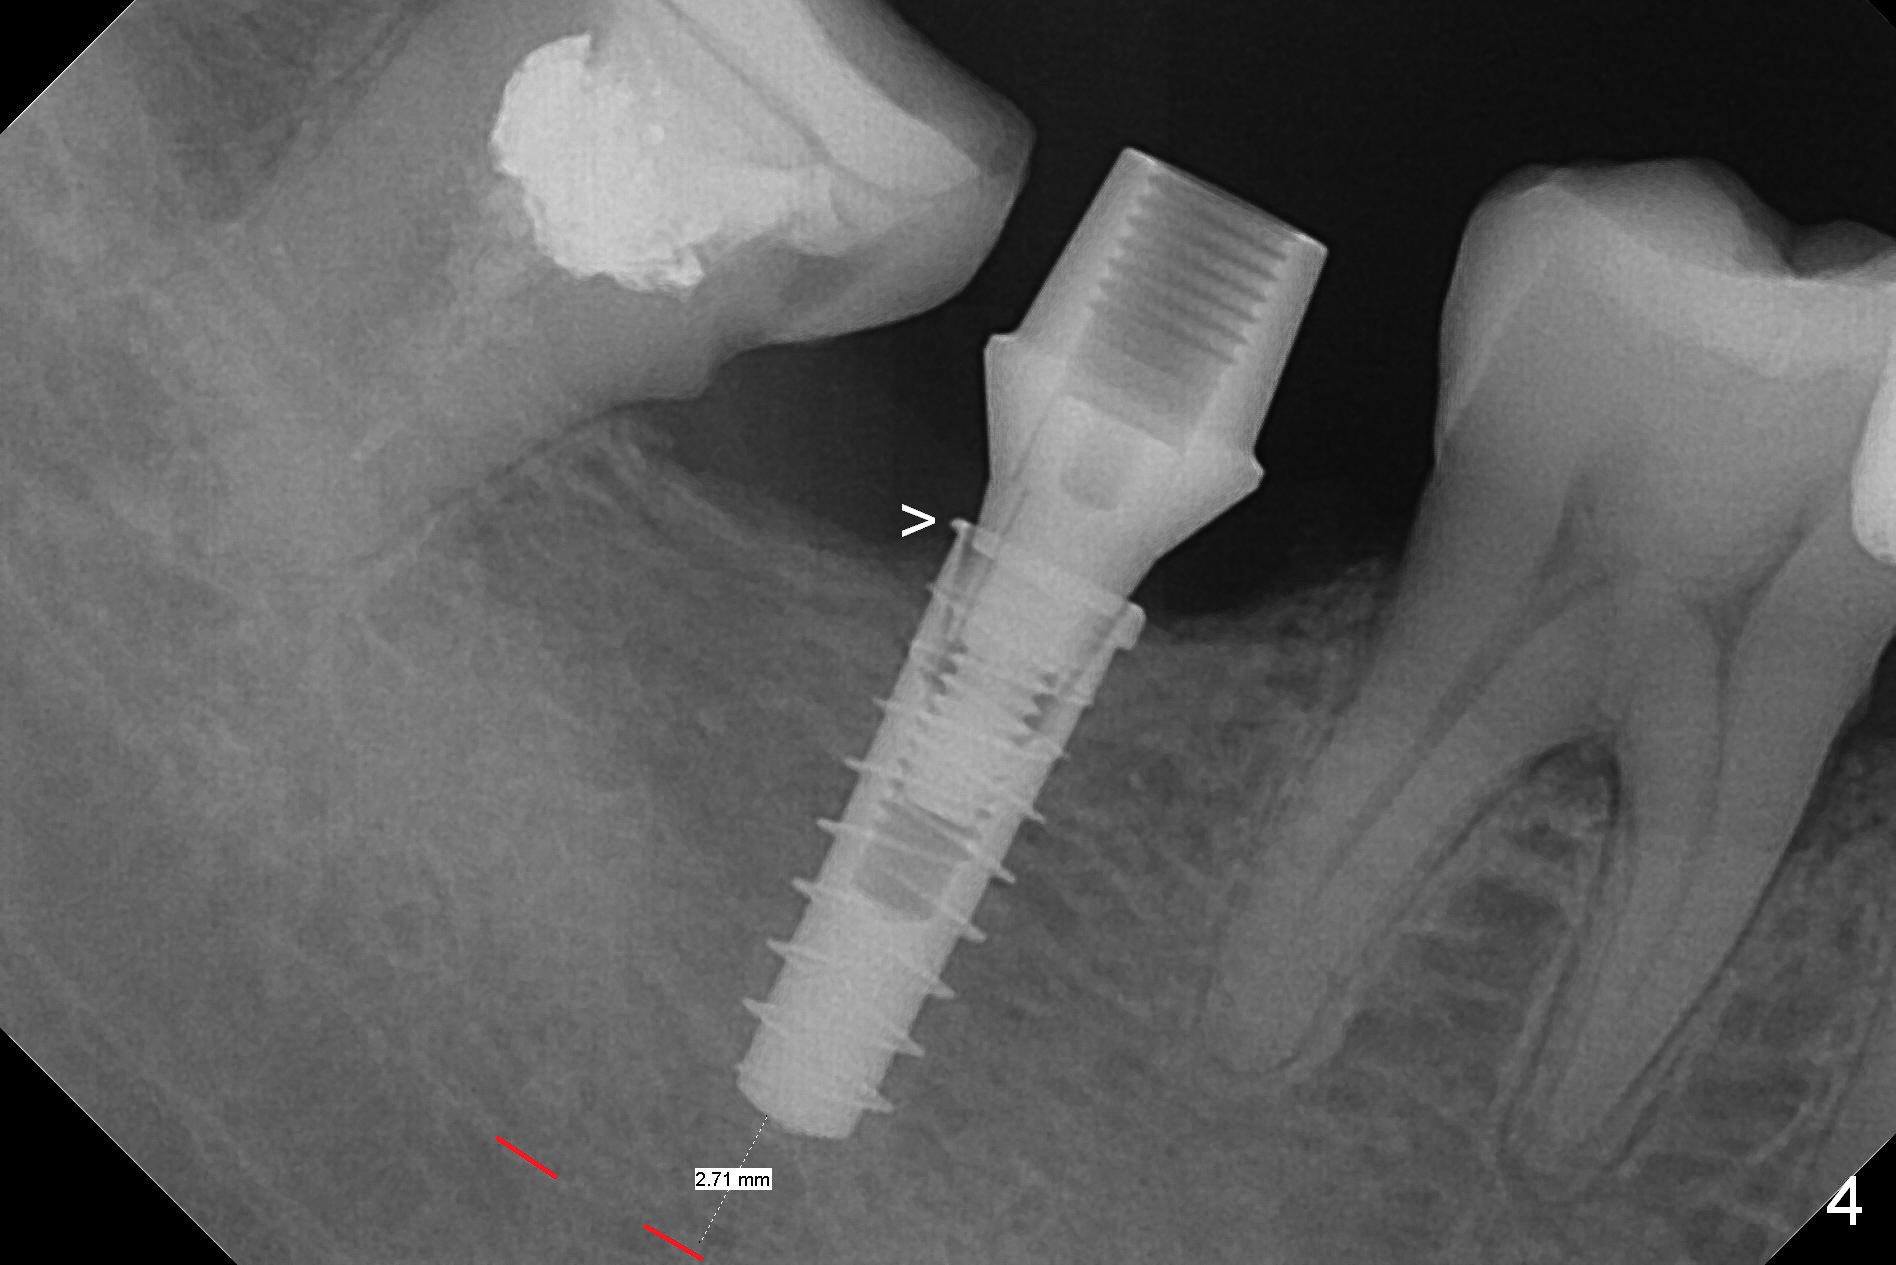

The ridge at #31 is also narrow buccolingually (Fig.1 *).  After incision and 1.6 mm pilot drill, a guide pin with 7 mm length is inserted to confirm trajectory and depth; it appears that 11 mm osteotomy has enough clearance from the superior border of the Inferior Alveolar Canal (IAC, Fig.2 red dashed line).  Following Marking Bur, 3.3 mm Magic Drill and final drill, the buccal plate seems to be thin (Fig.3 *).  When a 4x11 mm IBS implant and 5x4(2) mm pair abutment are placed, the distal thread is exposed (Fig.4 >), the abutment contacts the opposing tooth (data not shown) and there is 2.7 mm clearance from IAC.  After increasing the osteotomy 1-2 mm, the implant is placed deeper; the autogenous bone with Osteogen is placed around the plateau of the implant (Fig.5 >), particularly buccally, followed by collagen membrane.  When sutures are placed around the abutment, the buccal ridge looks bulkier (Fig.6) than preop (Fig.1).  It may remains so long term.  The flap surgery makes it possible for simultaneous GBR and reduction in possibility of peri-implantitis.  Last, periodontal dressing is applied.